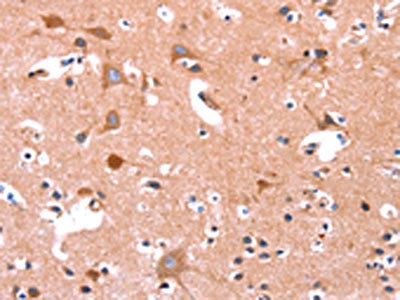

The image on the left is immunohistochemistry of paraffin-embedded Human brain tissue using CSB-PA196653(ABI1 Antibody) at dilution 1/40, on the right is treated with synthetic peptide. (Original magnification: ×200)